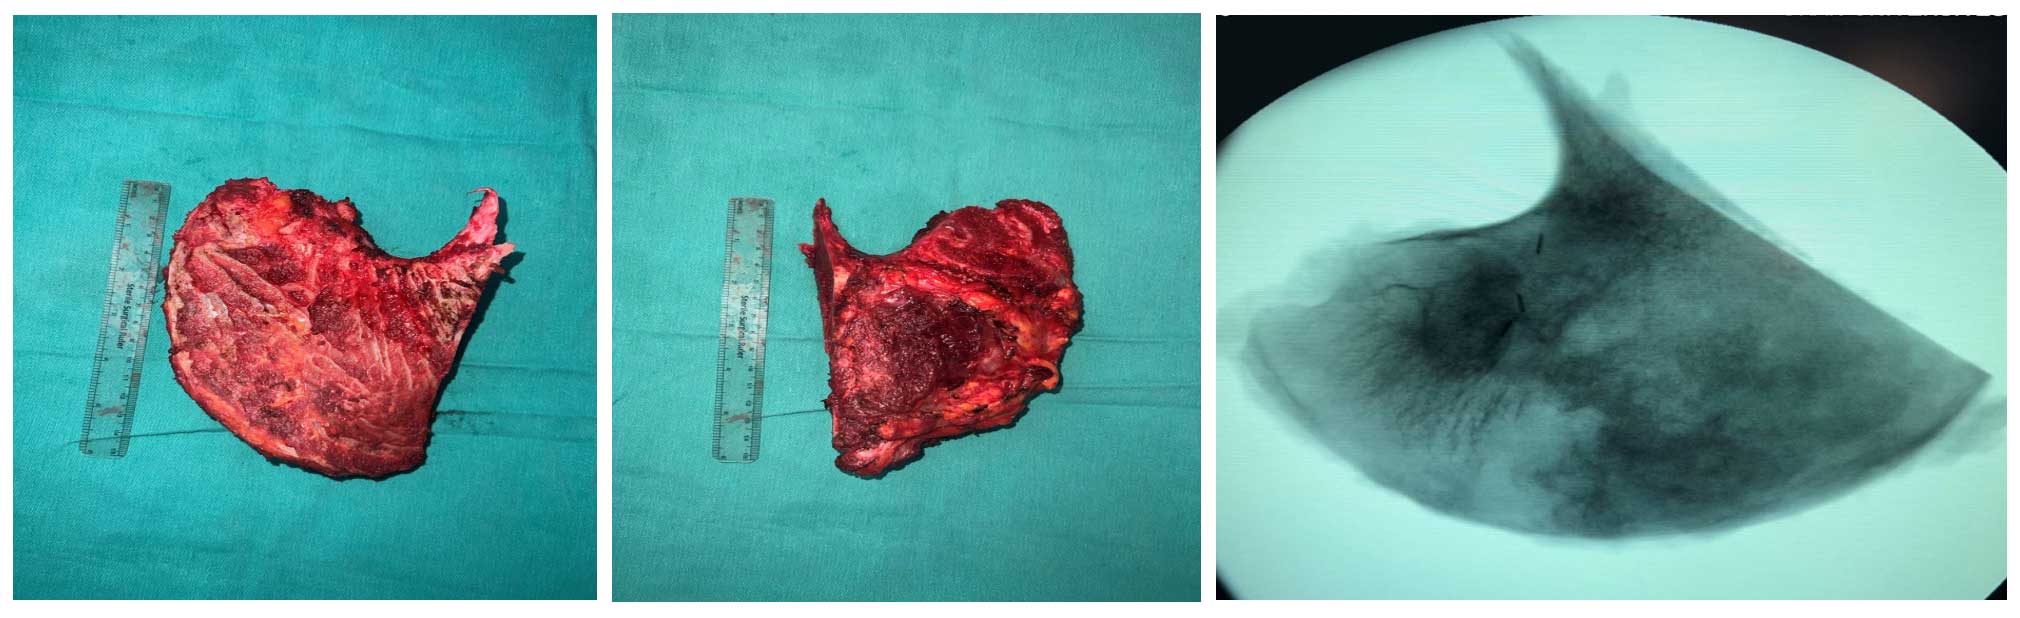

Ameliyat Esnası: Çıkarılan tümör dokusunun klinik ve skopi görüntüsü.